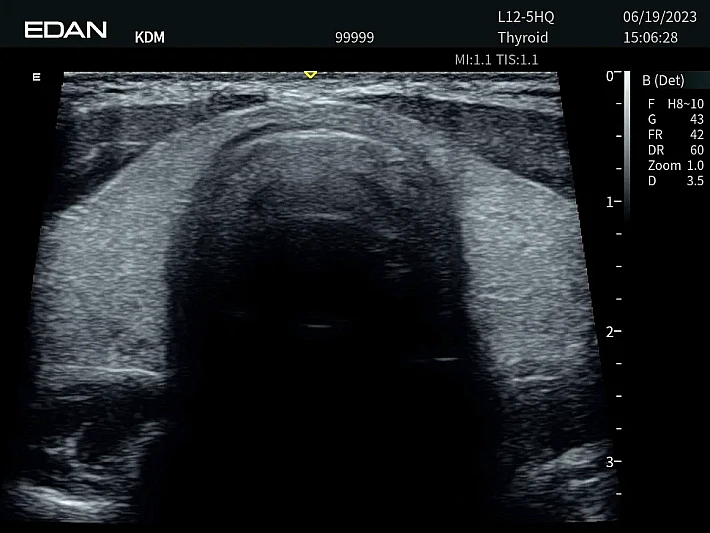

Медицинское оборудование и сервисное обслуживание